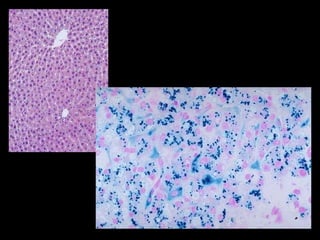

Pigmentos Exógenos Pneumoconioses Carvão (antracose) Sílica (silicose) Asbestos (asbestose) Outras: Tatuagem

Pigmentos Exógenos PneumoconiosesCarvão (antracose) Sílica (silicose) Asbestos (asbestose) Outras: Tatuagem